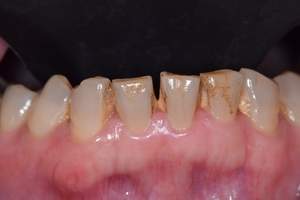

歯石除去

治療前

治療後

| 年齢 | 25歳・男性 |

| 主訴 | 歯石をとりたい・検診 |

| 治療内容 | 各種検査・歯石除去 |

| 治療期間 | 60分 |

| 費用 | 初診料3,000〜4,000円前後 +歯石除去約1,000円 |

| リスク・副作用 | ・処置後に歯がしみることがあります。 ・歯と歯の間に隙間ができるので、息が漏れ発音しにくいと感じることがあります。 ・歯ぐきの炎症が軽減すると歯ぐきが引き締まり、歯が長く見えることがあります。 |

| 担当者所見 | 前歯の裏側にすぐに歯石が溜まってしまいザラザラして気になるとご相談いただいたので適切な歯ブラシの当て方とフロスの通し方をお伝えさせて頂きました。 |